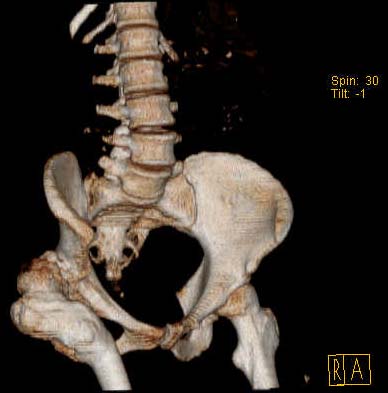

Наше общее мнение - проведение клиновидной остеотомии в зоне дополнительной точки опоры с ее иссечение и укорочением бедра, протезирование ножкой Вагнера.

Похожий случай представляем на ретгенограммах. Операция выполнена в 1996 г.